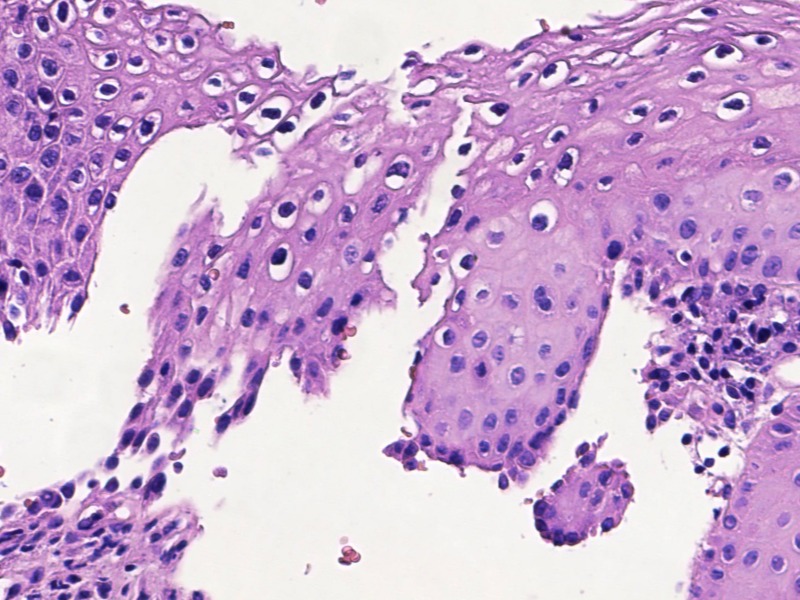

宫颈活检高级别?

TCT:ASC-US HPV:52+

宫颈活检

1、宫颈活检:灰白组织9块,直径0.3-0.5cm,质软,全取包。

图1

LSIL。

基底样细胞没有那么多,低级别够了